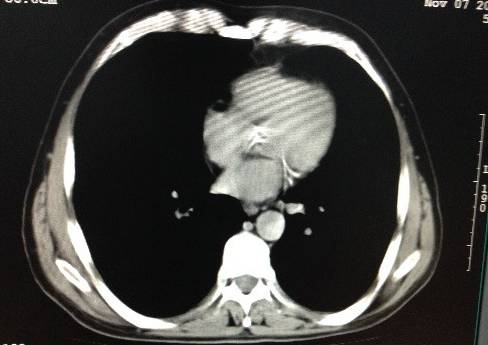

随着年龄的增长,动脉血管的弹性日益减退,就像塑料或橡胶管子一样,用久了自然就会变硬。严重者则可表现为动脉钙化,在X线片子上能看到发白的密度增高影像。

顾名思义,动脉粥样硬化是发生在动脉壁上、呈粥样的硬化斑块,是由于动脉壁的内皮细胞受到破坏后脂质沉积形成的,斑块也可逐渐变硬,形成钙化。

临床上,将动脉粥样硬化斑块分为软斑块、硬斑块、混合型斑块三种。其中, 软斑块常常不稳定,容易破裂、形成血栓,堵塞动脉血管,使下游的动脉血供减少甚至中断。它就像血管中的“定时炸弹”,若发生在给心脏供血的冠状动脉,则会形成心绞痛,甚至急性心肌梗死、猝死。